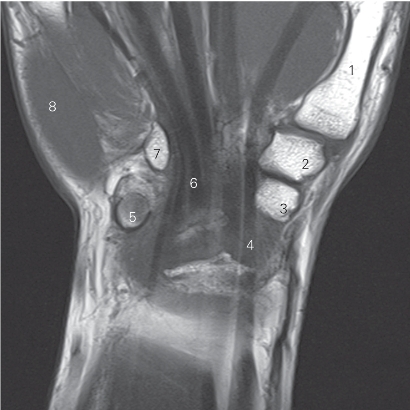

图4-53 经大多角骨的冠状断层MR T1加权图像

1 第一掌骨 1st metacarpal bone 2 大多角骨 trapezium bone

3 舟骨 scaphoid bone

4 拇长屈肌腱 tendon of flexor pollicis longus

5 豌豆骨 pisiform bone

6 指深屈肌腱 tendon of flexor digitorum profundus

7 钩骨钩 hamulus of hamate bone 8 小鱼际 hypothenar